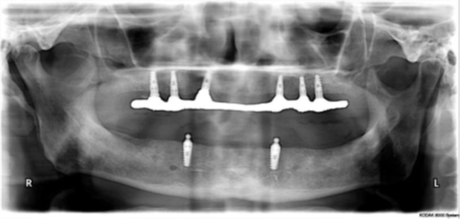

The clinic is equipped with modern dental technology, digital diagnostics, and advanced implant systems to ensure precise and predictable results. Every patient undergoes a detailed consultation and evaluation before the procedure to determine the best treatment plan.

Dental implant treatment requires specialized training and expertise. At Dental Lifecare, implant procedures are performed by Dr. Vijay Prakash Gupta Prosthodontist and Implantologist, a highly experienced specialist with 22 years experience in Implantology.

As a skilled Implantologist in Noida, Dr. Gupta has successfully treated thousands of patients with missing teeth. His expertise in prosthodontics and implant dentistry allows him to restore both function and aesthetics with precision.

- Advanced dental technology and modern equipment